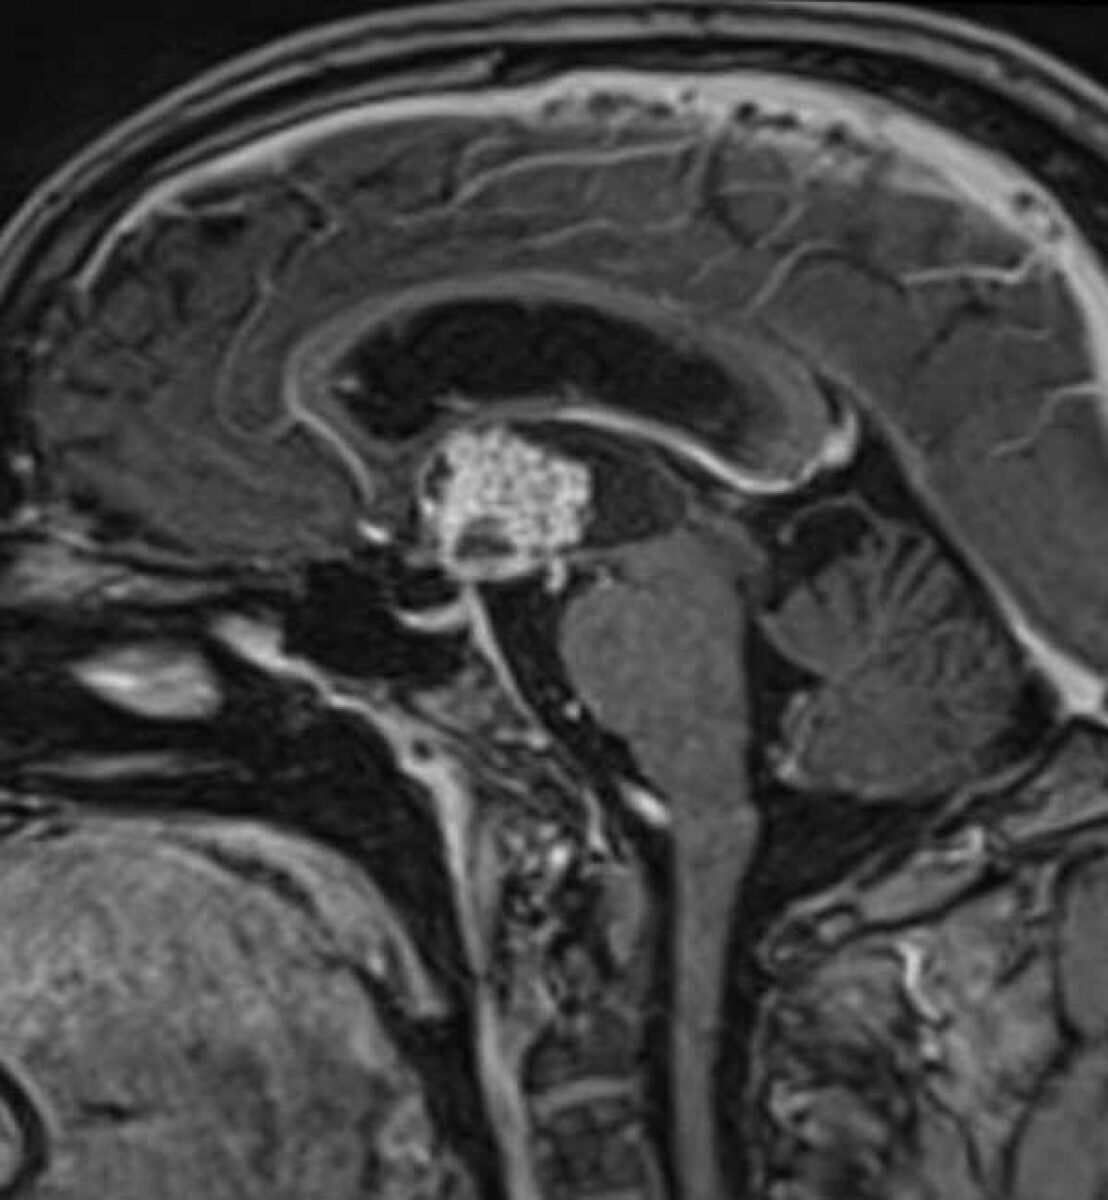

Πρόκειται περί όγκου που αναπτύσσεται στην περιοχή της υπόφυσης, της υπερεφιππιακής δεξαμενής (χώρος γεμάτος με

εγκεφαλονωτιαίο υγρό στον οποίο βρίσκονται το οπτικό χίασμα, ο μίσχος της υπόφυσης καθώς και αγγεία του εγκεφάλου), του υποθαλάμου και της 3ης κοιλίας του εγκεφάλου. Παρουσιάζεται συνήθως σε παιδιά ή νέους ενήλικες και αντιπροσωπεύει περίπου το 10% του συνόλου των όγκων του εγκεφάλου σε νέους. Μπορεί ωστόσο να διαγνωσθεί σε οποιαδήποτε ηλικία.

Το κρανιοφαρυγγίωμα είναι καλοήθης όγκος. Αναπτύσσεται όμως σε μία ιδιαίτερα ευαίσθητη περιοχή του εγκεφάλου και σχεδόν πάντα περιβρογχίζει τις ανατομικές δομές ή/και διηθεί τον εγκεφαλικό ιστό. Αναπτύσσει αποτιτανώσεις (επασβεστώσεις) καθώς και ιδιαίτερα ευμεγέθεις κύστεις, που καθιστούν πολλές φορές τη θεραπεία ιδιαίτερα δύσκολη.

Κρανιοφαρυγγίωμα